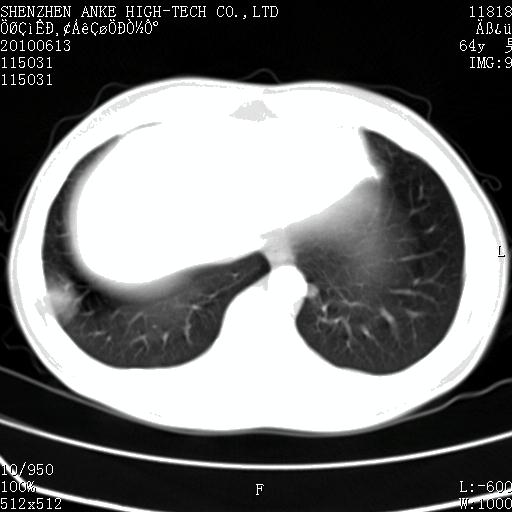

以下是引用beifangren在2010-7-26 22:05:00的发言:[br]左肾中极圆形占位,肾盏肾盂受压移位,建议增强。结合肺部结节。肝低密度灶,多为肾癌并肺部、肝转移。